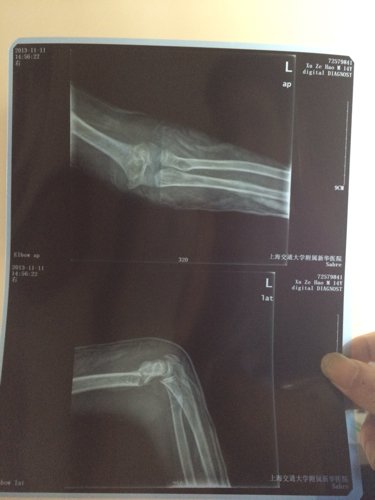

小儿十四周岁,一周前跳绳,不小心用手一撑造成肱骨骨折,这是复位一周后的X光片情况,请医生提供治疗建

病情分析: 您好;骨折应该手术治疗的。只有骨折固定稳定,才容易愈合。 指导意见: 建议您还是选择髓内针固定比较好,髓内针固定对骨折处的组织剥离少,血运破坏也少,有利于骨折愈合。另外术后早期活动,没有偏心力,不容易造成再骨折和内固定锻炼的情况。